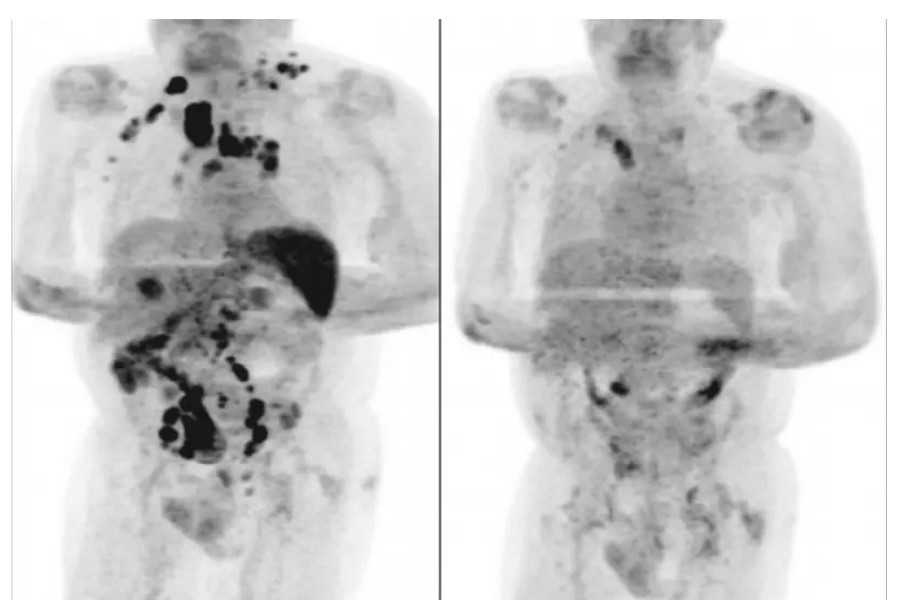

Quatro meses depois, os médicos afirmaram que o inchaço dos nódulos havia diminuído. Um exame de tomografia revelou a remissão generalizada do linfoma.

A hipótese levantada pelos autores do artigo é de que a infecção pelo novo coronavírus desencadeou uma resposta imune contra o tumor. As citocinas inflamatórias produzidas em resposta à infecção poderiam ter ativado células T específicas com antígenos tumorais e células que naturalmente agem contra o tumor.